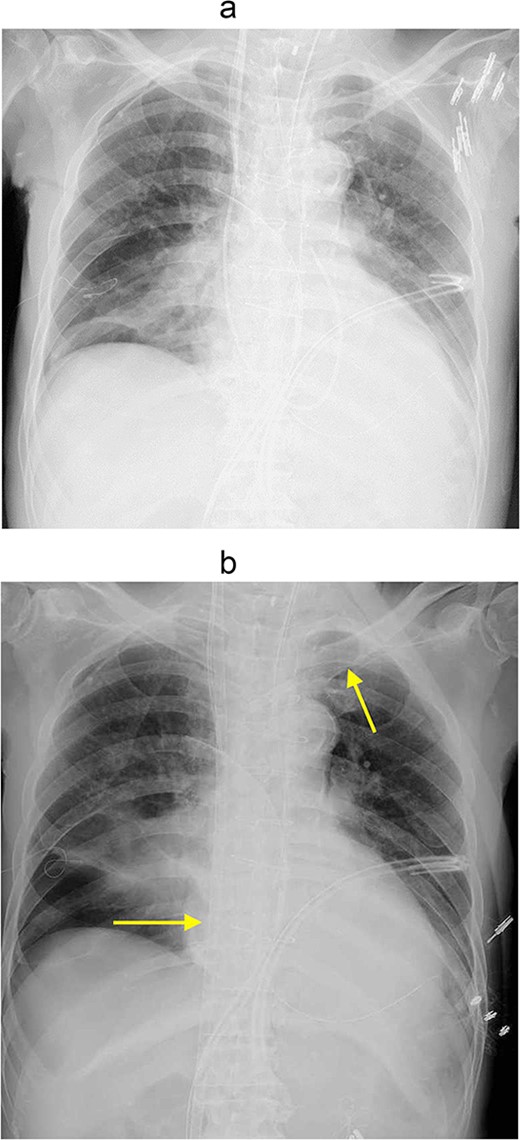

However, 3 hours after entering the intensive care unit (ICU), PaO2/FiO2 ratio was severely reduced to the 70s (Fig. 1a). It was necessary to apply high PEEP for cardiogenic shock with pulmonary edema, but the higher the PEEP, the more air leakage there was. Although hemodynamics was stable, his respiratory status was poor and reoperation was deemed difficult. Therefore, VV-ECMO was atarted on postoperative day (POD) 2. To facilitation mobilization and rehabilitation to improve lung oxygenation, cannulas were not inserted through the groin; a drainage cannula was inserted via the right internal jugular vein to the vena cava inferior and oxygenated blood was perfused into the left subclavian vein (Fig. 1b). On POD3, oxygenation has improved and the patient was extubated. He was managed with VV-ECMO inserted, as air leak was still allowed. On the same day, rehabilitation intervention was also started (Fig. 2). The air leak disappeared on POD4, and the VV-ECMO was removed on POD6. He was discharged from our hospital on POD13, and 6 years after the surgery, he is still alive and well.

(a) Chest Xp immediately after the operation. (b)

Chest Xp after VV-ECMO (arrow: venous cannulations).